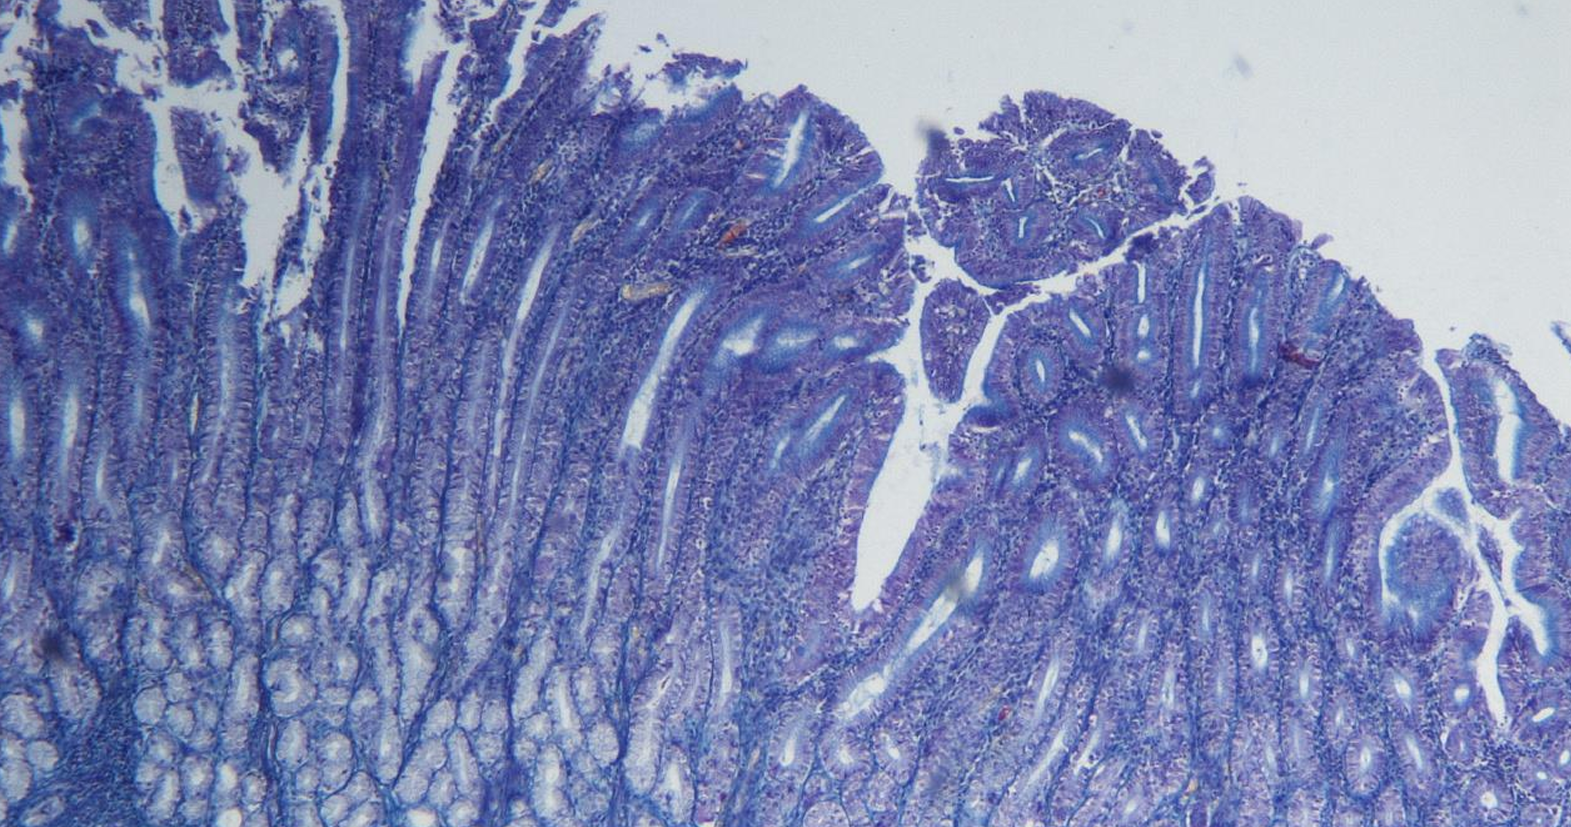

intestino grueso es la parte final del sistema digestivo, encargada de absorber agua y electrolitos, además de formar y eliminar las heces.

intestino grueso

colon